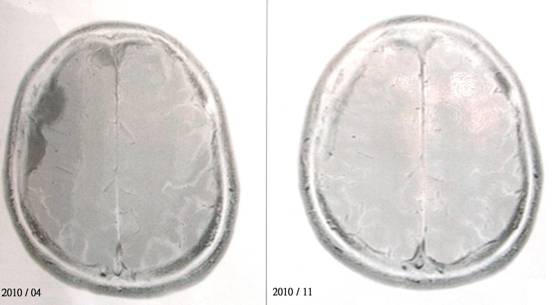

十方大德您好,佛弟子法因于20104月發現得到腦瘤,經過8個月的治療,目前已經痊癒,腫瘤都消失不見。我想我應該有點資格可以回答您這個問題。

(編者附記:這種嚴重的疾病,還要能將中國固有的食療法用上,以輔助身體細胞修復為主,如攝食高倍(x18)靈芝、五行蔬果湯、細胞食物(cellfood)、…等不傷身體的食療法。病者恢復後,還要記得繼續保養,自己病中做了什麼樣的處理,癒後還是要照樣地如法繼續照顧自己的身體與繼續如法的生活方式來生活。末後附相片─左圖腦部黑影處是腫瘤,右腦圖已不見了!)